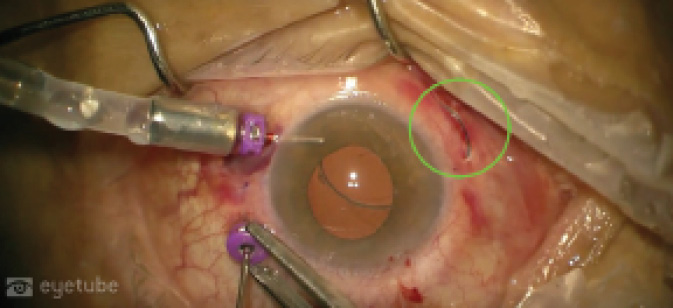

The externalized haptic was retracted as much as possible on the conjunctiva to allow visualization of the other intraocular haptic through the pupil. Using the same sequence of steps, the second haptic was also then externalized (Figure 1).

Figure 1. After the first haptic was externalized (green circle), the second cannula was removed with serrated forceps and the other haptic was externalized.